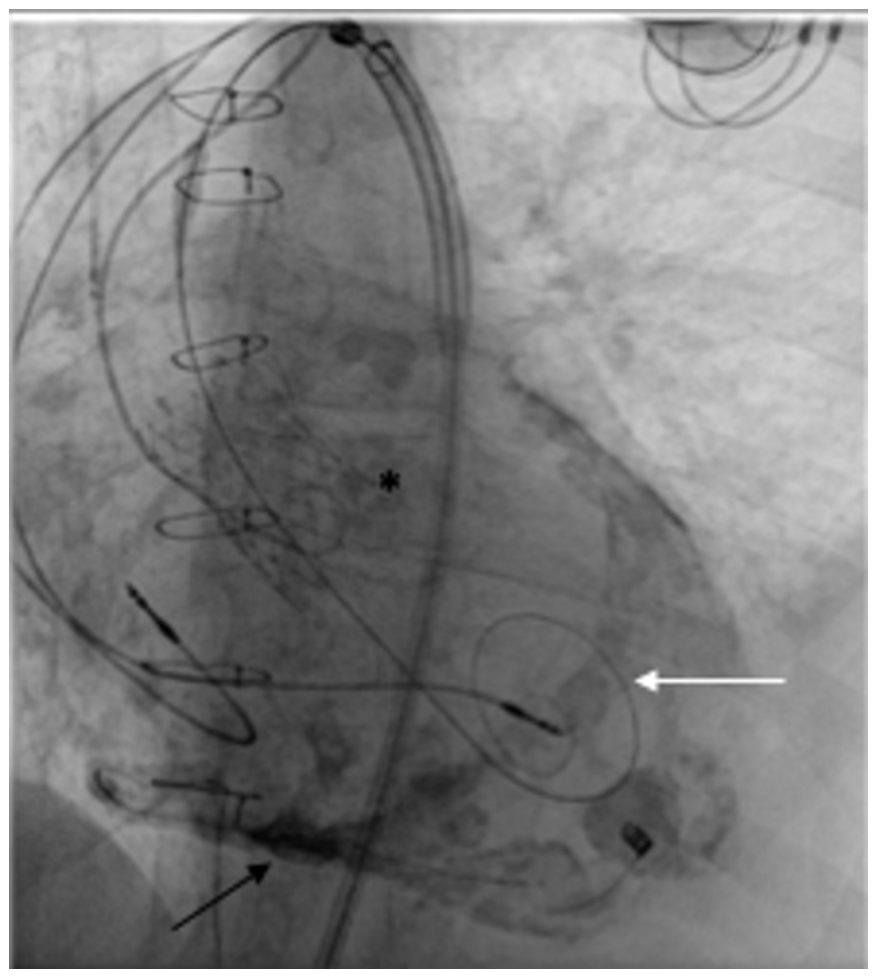

Gated cardiac computed tomography (Figure 1) revealed extensive eccentric calcification of the left ventricular outflow tract (LVOT) extending into the mitral valve leaflet and a large aortic annulus (33 mm; mean annular diameter/area, 854 mm2). This is larger than all recommended manufacturer annular size limits, although observational data support the use of both Edwards Sapien 3 and Medtronic Evolut R in such annuli. In this case, the extent of LVOT calcification significantly increased the risk of annular rupture with a balloon-expandable valve. Hence, a self-expanding, 34-mm Evolut R valve was chosen and deployed successfully via the femoral route (Figure 2).